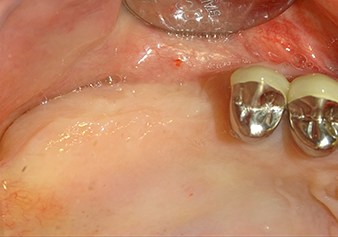

Une patiente de 49 ans, non fumeuse et sans antécédents médicaux remarquables, a été orientée vers notre cabinet de chirurgie orale pour l’extraction chirurgicale de la dent 16 préalable à la pose d’un implant. Après l’extraction, la patiente a rencontré de légers problèmes de sinusite, à la suite de quoi nous avons commencé par attendre six mois avant de prendre la mesure. À l’endroit prévu pour la pose de l’implant, l’os résiduel mesurait 3-4 mm de haut (Fig. 1 et 2).